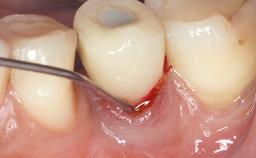

In this case, Nicola Zitzmann describes the sudden loss of a previously well-osseointegrated implant that had been in healthy function for 5 years. The case includes recommendations for occlusion and function of implant restorations. A 74-year-old patient had received implant-fixed dental prostheses in the maxilla in 2008, and in the right mandible three years later. His tooth loss was mainly related to recurrent caries associated with hyposalivation as a potential side effect of his cholesterol-lowering medication.